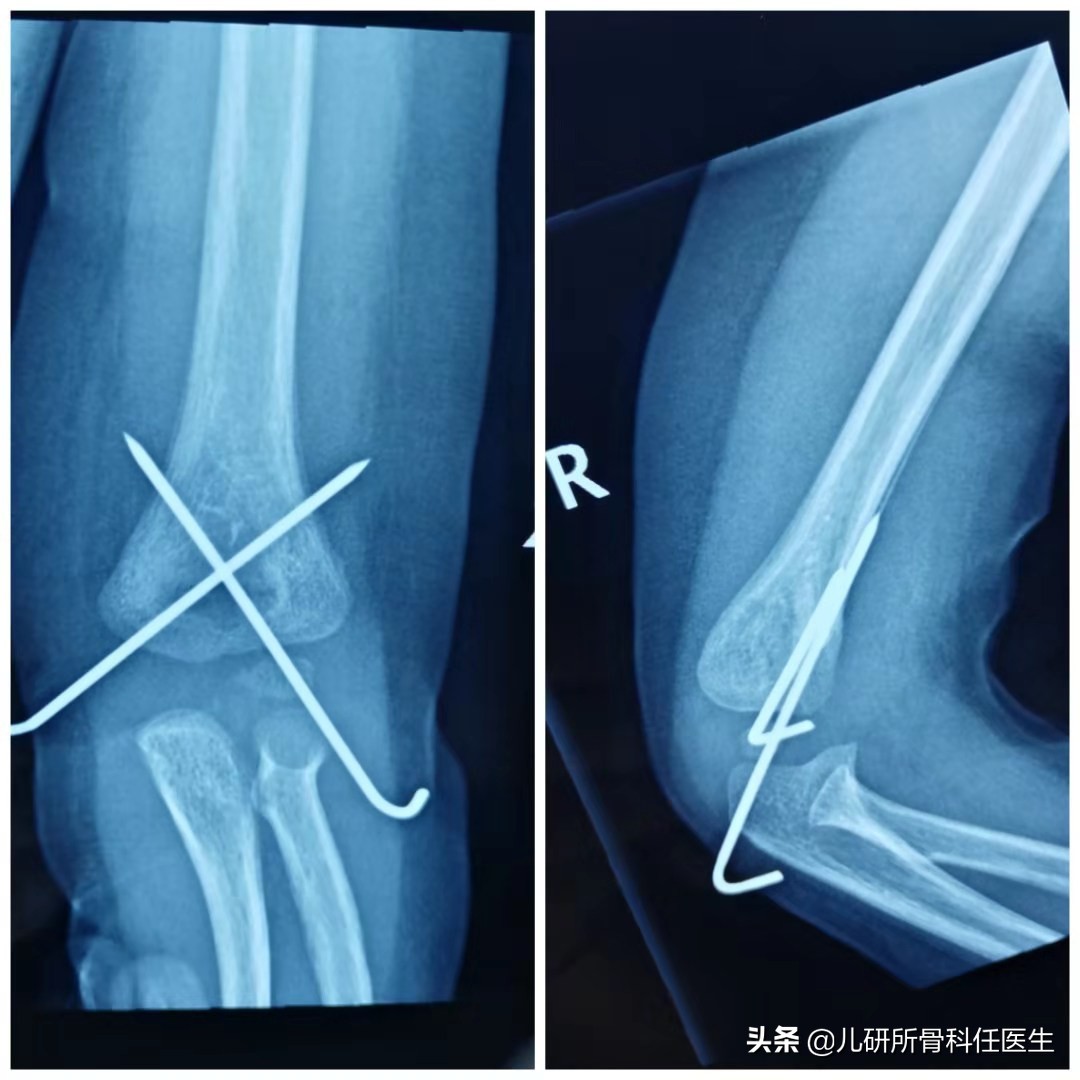

5岁的男孩淘淘,一点都不老实,1个月前因为摔了一跤,把肱骨给摔骨折了。急诊就诊诊断为肱骨髁上骨折,当晚任医生就给做了手术,放了两根克氏针,针尾留在了皮肤外面。今天门诊来复查,淘淘姥姥迫不及待说“医生,我家孩子打的是钉子(克氏针),啥时候取合适?”对于淘淘这种上肢骨折,一般术后3-4周就可以拆除石膏,克氏针一般在术后3-4周拆除;对于年龄偏大、骨折较重等情况,石膏和克氏针可以延长到5-6周拆除。下肢的股骨、胫骨是承重骨,骨折愈合时间和上肢差不多,但是,因为有负重的要求,一般要比上肢晚1-2周拆除。

对于克氏针针尾留置于皮肤外面的,可以在门诊拔除,不必住院。值得提醒的是,对于特别焦虑和对疼痛耐受力特别差的宝宝,可以住院给予镇定取内固定,避免给宝宝的心灵留下太大的创伤。克氏针针尾留置于皮肤以下的宝宝,需要住院行再次切开,取出克氏针。